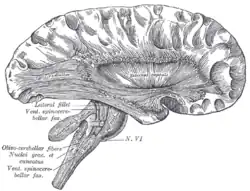

![]() Deep dissection of cortex and brain-stem. (External capsule visible at center.) | |

The external capsule is a series of white matter fiber tracts in the brain. These fibers run between the most lateral (toward the side of the head) segment of the lentiform nucleus (more specifically the putamen) and the claustrum.

The external capsule is a route for cholinergic fibers from the basal forebrain to the cerebral cortex.

The putamen separates the external capsule from the internal capsule medially and the claustrum separates it from the extreme capsule laterally. But the external capsule eventually joins the internal capsule around the lentiform nucleus.